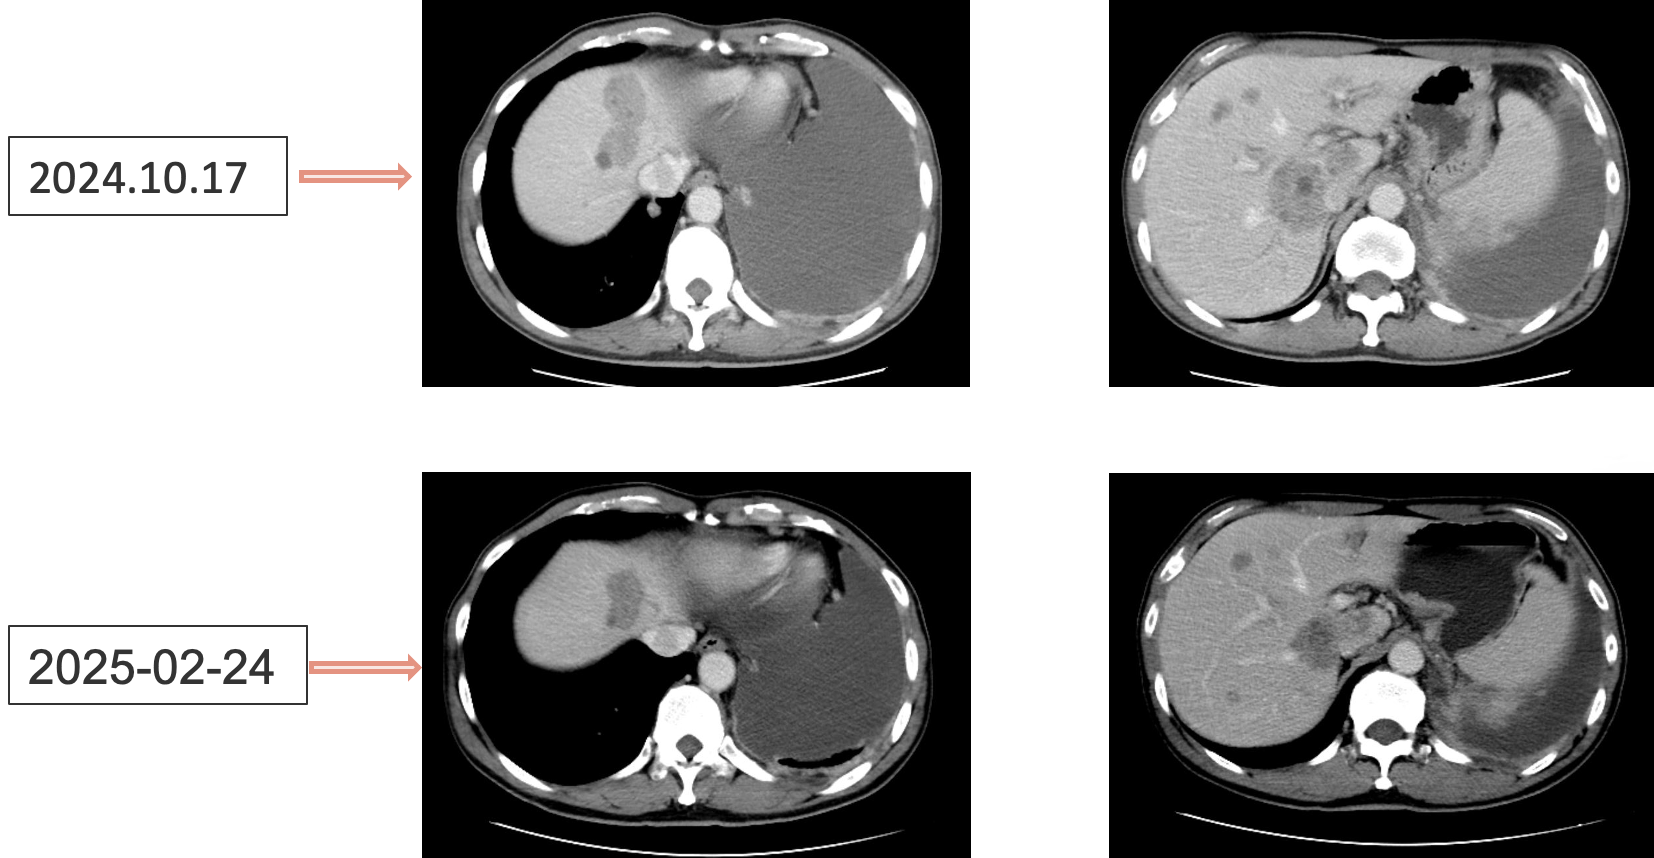

艾托组合抗体治疗:2024年10月至今

患者采用艾托组合抗体(PD-1/CTLA-4组合抗体)联合卡铂和安罗替尼治疗,同时进行血管内皮抑素胸腔灌注控制胸水。第一周期治疗后出现发热气喘等不良反应,经对症处理后症状改善。6周期治疗后影像学评估显示肺部病灶明显缩小,肝脏及淋巴结转移灶缩小,胸腔积液减少,疗效评价为PR(部分缓解),患者临床症状明显改善,生活质量显著提升。

1. 艾托组合抗体联合方案治疗6周期后,患者肺部病灶明显缩小,肝脏及淋巴结转移灶缩小,胸腔积液减少,疗效评价为PR(部分缓解);

治疗结果证实我们的选择是正确的。患者接受艾托组合抗体联合卡铂和安罗替尼治疗后,肿瘤病灶明显缩小,肝脏及淋巴结转移灶缩小,胸腔积液减少,临床获益显著,疗效评价为PR。

姚菲教授:在本例患者的治疗过程中,艾托组合抗体联合化疗和抗血管生成药物治疗对免疫治疗耐药及多线治疗后进展的NSCLC患者显示出良好疗效。患者迅速获得临床缓解,影像学评估显示病灶明显缩小,体现了艾托组合抗体克服PD-1抑制剂耐药的特性,该例患者免疫再治疗挑战成功。